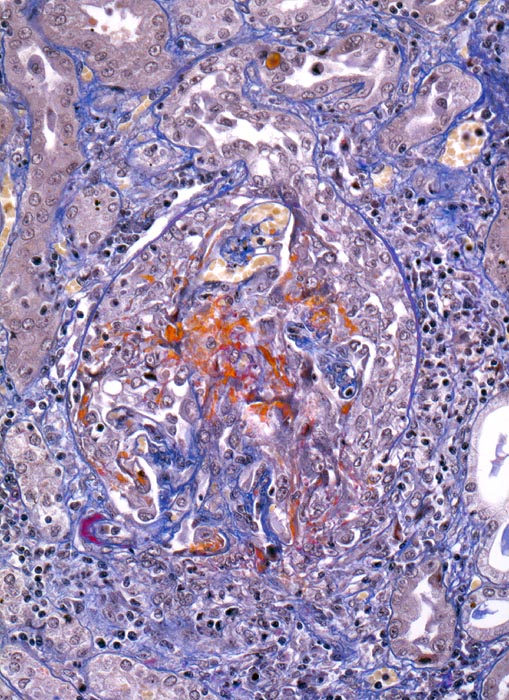

extrakapilläre Glomerulonephritis bei Morbus Wegener

Glomerulum mit Harnpol und Gefässpol mit geringer Arteriolosklerose des Vas afferens. Ausgedehnte Schlingennekrosen mit Exsudation von Fibrin und Ausbildung eines frischen rein proliferativen globalen Halbmondes. Einzelne erhaltene Schlingen sind ausgeweitet. Über der Schlingenruptur ist auch die Bowman'sche Kapsel rupturiert. An dieser Stelle findet sich eine periglomeruläre chronische Entzündung.

Rapid progressive Glomerulonephritis mit Entwicklung einer Oligurie innert weniger Tage. Fieber und Nachtschweiss. Chronische Sinusitis. cANCA erhöht.